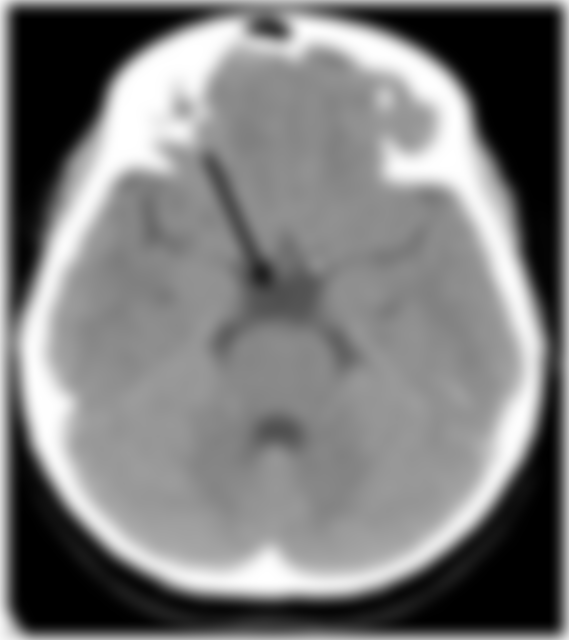

37.頭部電腦斷層攝影呈現如下圖,箭號所指何者最正確?

(A)側腦室

(B)第三腦室

(C)第四腦室

(D)第五腦室